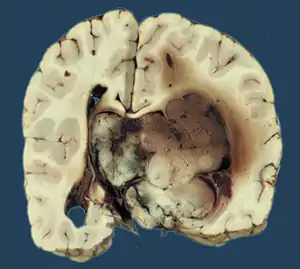

Choroid plexus papilloma

Choroid plexus papilloma, also known as papilloma of the choroid plexus, is a rare benign neuroepithelial intraventricular WHO grade I lesion found in the choroid plexus.[1] It leads to increased cerebrospinal fluid production, thus causing increased intracranial pressure and hydrocephalus.[2]

Choroid plexus tumors are divided into three categories by the World Health Organization (2016):[9] papillomas (grade I), atypical tumors (grade II), and carcinomas (grade III). Less than two mitotic figures per 10 high power fields are present in CPPs, two to five are present in atypical ones, and more than five are present in carcinomas. The tumors are visible as pink, soft, spherical lumps with erratic projections and considerable vascularity.

Histopathology